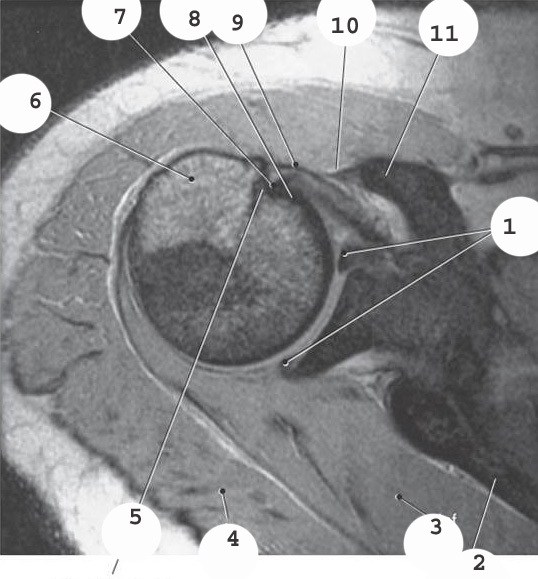

7

supraspinatis muscle

5

glenoid

4

deltoid

3

acromion

2

labrum

1

bicep